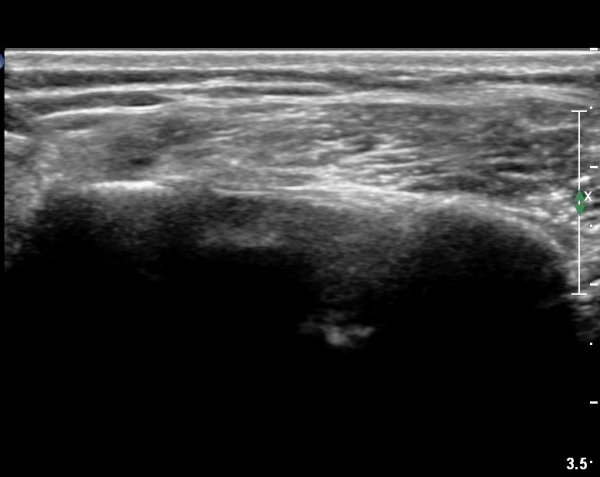

±Ø»ó°Ç Á¶´ã¸é°Ë»ç¿¡¼­ ±Ø»ó°ÇÀÇ ÅðÇ༺º¯È­È­ ºÎºÐÀûÀÎ ÆÄ¿­ÀÌ  °üÂûµÇ¸é ´ë°áÀýÀº

ºñÈĵǾî ÀÖ´Ù(»çÁø 6, 7, 8).